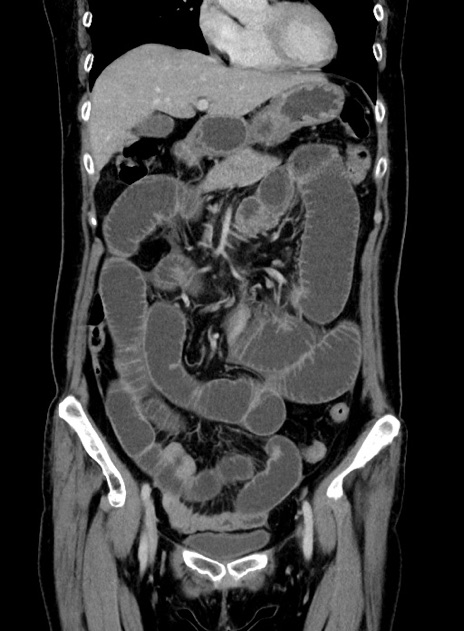

症例9(冠状断像)

【症例】 60歳代女性

【主訴】むかつき、みぞおちの痛み

【現病歴】3日前よりむかつきがあり、食事がとれない。

【既往歴】糖尿病

【身体所見】発熱なし、心窩部圧痛軽度あるも、腹膜刺激症状なし。

【データ】WBC 7400、CRP 1.92